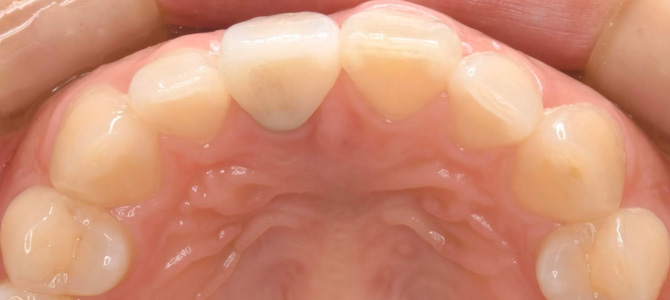

治療後の口腔内写真。

治療開始から3ヶ月後に、美しい上部構造(セラミック歯)が入りました。

まだ歯茎のラインは不揃いですが、1ヶ月後には更にキレイに治ってきます。

裏側から見ても、天然の歯との違いがわからない仕上がりにできました。